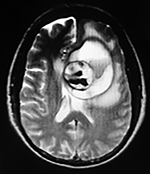

EJEMPLO DE CASO CLÍNICO (8)

Paciente femenino de 29 años de edad con historial de cefalea crónica que presenta súbitamente disdiadococinesia y dismetría izquierda.

El estudio de RMN presenta una lesión bien circunscrita en hemisferio cerebeloso izquierdo con periferia de predominio hiperintenso en T1 y T2, y centro hipointenso, edema perilesional mínimo, así como una imagen de un vaso venoso alimentador que recorre hacia el ángulo pontocerebeloso izquierdo.

Se realizó una craniectomía suboccipital paramedial derecha, así como un abordaje transcortical en el hemisferio cerebeloso izquierdo llegando a la región perilesional de aspecto amarillento, posteriormente se observa una lesión oscuro-verdoso de contenido hemático antiguo, retirando la cápsula y su contenido en la totalidad.

La evolución clínica de la paciente fue satisfactoria solo preservando la dismetría como secuela.

El resultado histopatológico fue consistente en angioma cavernoso.

El estudio de control de RMN se observa la brecha quirúrgica y ausencia de lesión (figs. 1, 2 y 3).

Figura 1:

Lesión cerebelosa izquierda ponderaciones en T1 y T2, la flecha señala vaso nutricio hacia el ángulo pontocerebeloso izquierdo, se puede observar el centro de intensidad heterogénea con contenido quístico multiloculado y edema perilesional leve.

Figura 2:

Cortes axiales en ponderación T1, cambios postquirúrgicos.